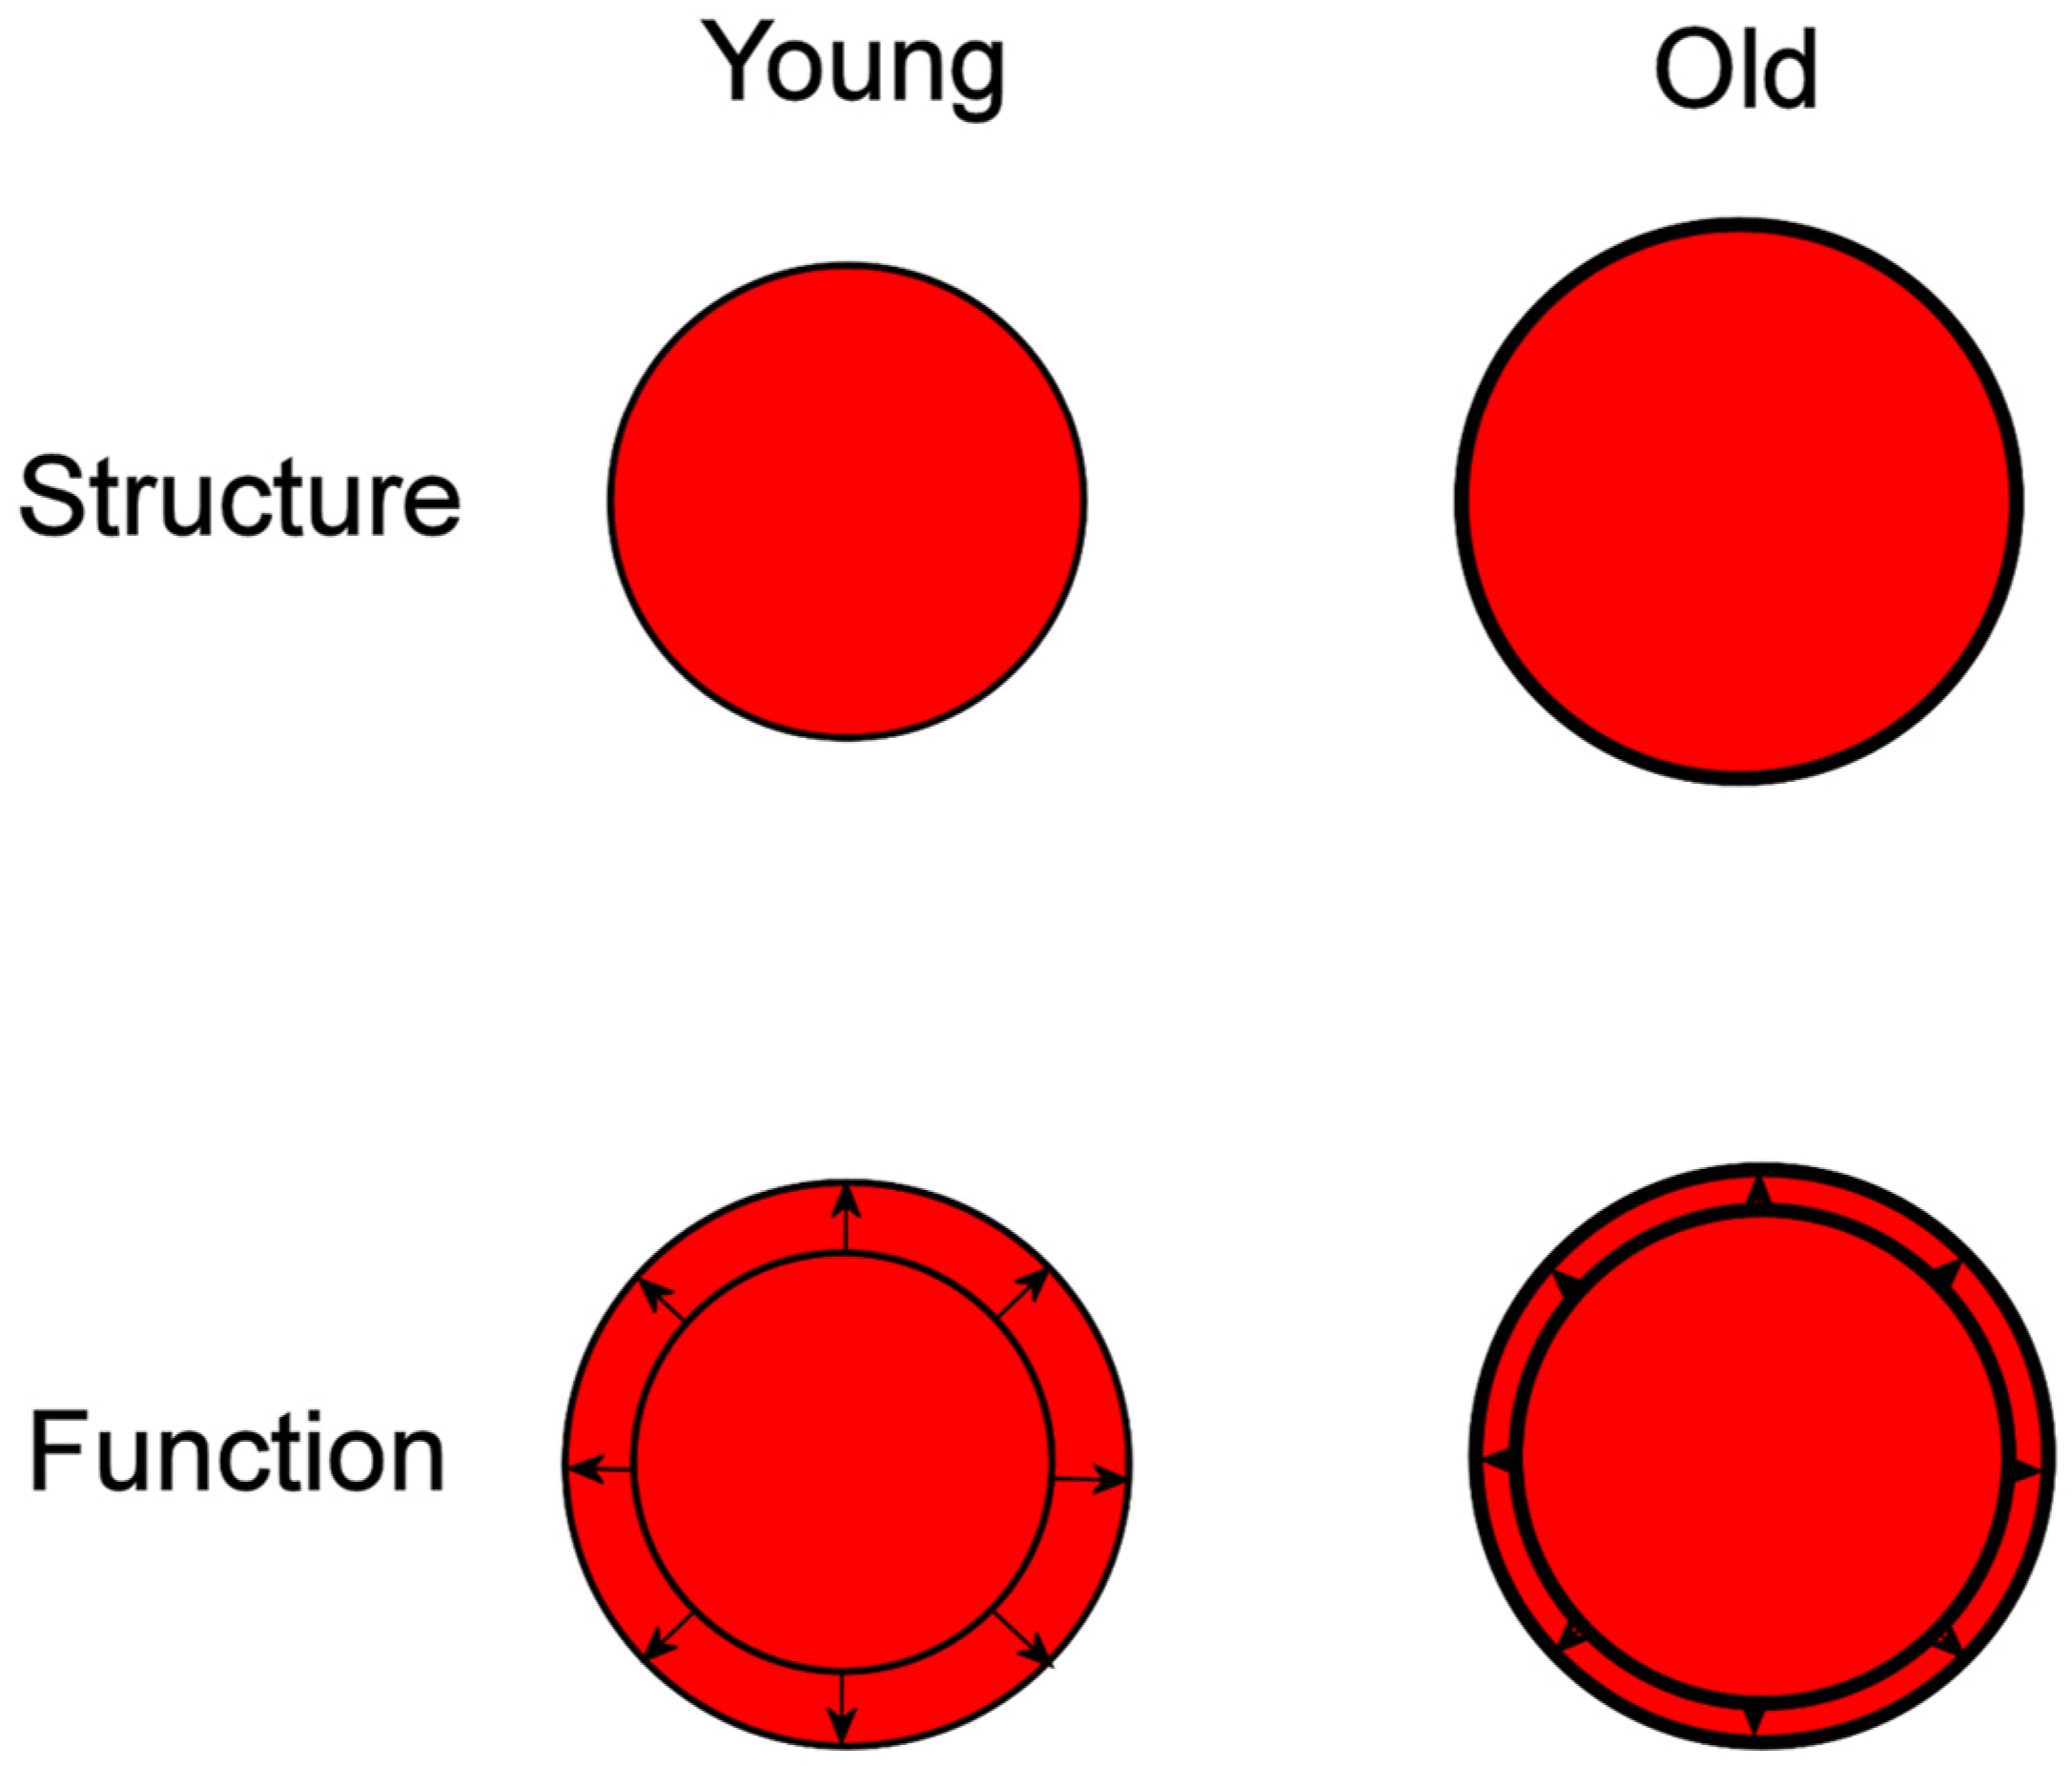

2. Vascular Aging

3. Cardiac Aging